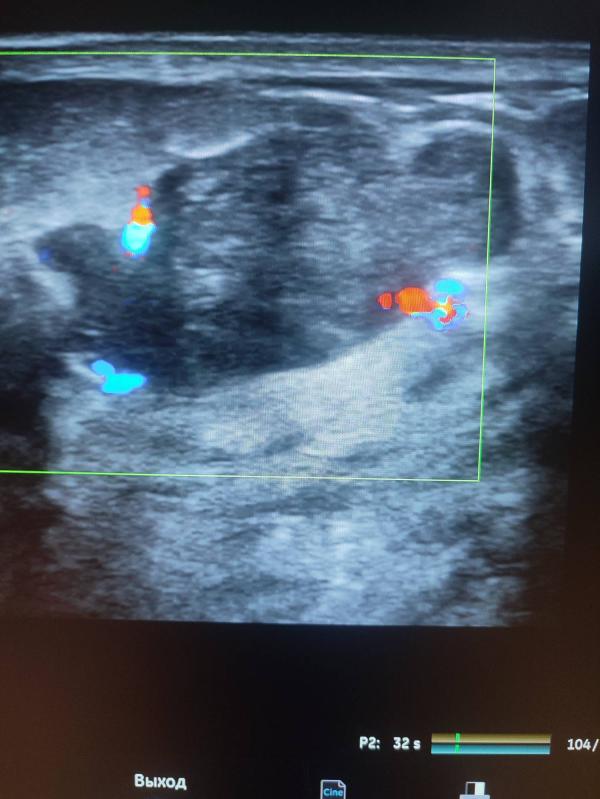

Добрый день девочки ! Хочу рассказать случай из практики: вчера у меня на приеме была девочка , возраст 31 год, планово готовилась на ЭКО, замужем 3 года! При УЗИ молочных желез было выявлено вот такие образования- точнее сказать рак левой молочной железы! В данном случае ни о какой беременности речи быть не может, тем более ЭКО ! Здесь длительное лечение , с последующей долгой реабилитацией! Самое интересное ,что она уплотнения отмечала давно , но к врачу не ходила ! (((